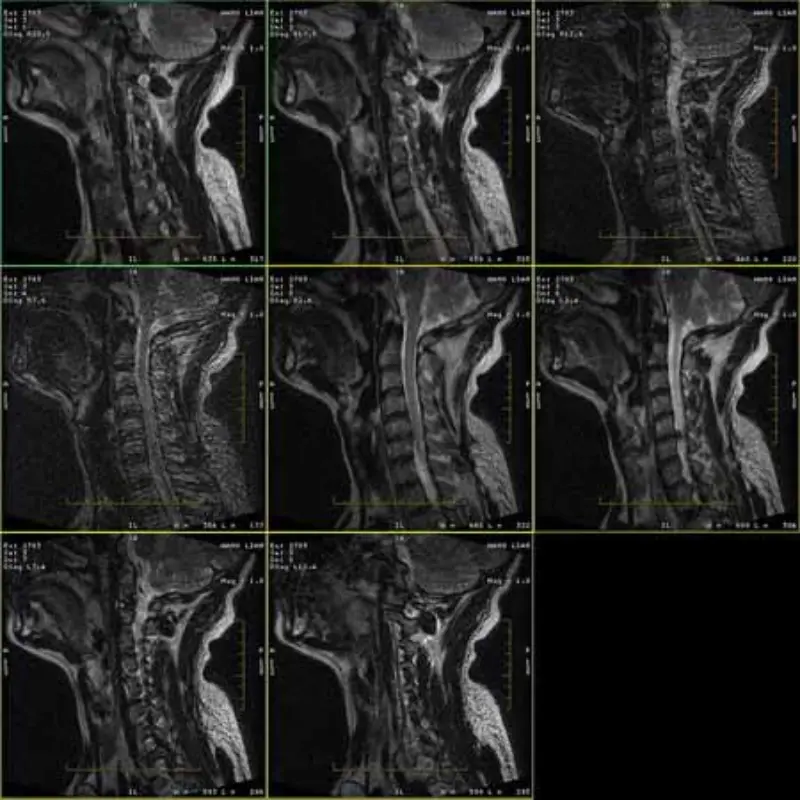

The images of FRFSE and GRE protocols has ghost and sometimes low SNR images appear in one series. But SE protocol images are normal.

Please look attach images.